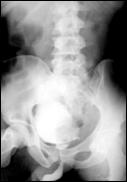

Cele mai multe metasteze la distanta, provocate de tumorile vezicale maligne, sunt localizate in plamani si in oase. Diagnosticul acestora se face prin: radiografii toraco-pulmonare, radiografii osoase sau scintigrame osoase (evidentiaza metastazele osoase cu 9-12 luni mai devreme decat expresia evidenta a acestora pe radiografiile standard).

4.5. Radiografia osoasa 4. Radiografia toraco-pulmonara

Figura 44. Metastaza in articulatia coxo-femurala

4. Scintigrama osoasa

Cele mai multe metasteze la distanta, provocate de tumorile vezicale maligne, sunt localizate in plamani si in oase. Diagnosticul acestora se face prin: radiografii toraco-pulmonare, radiografii osoase sau scintigrame osoase (care evidentiaza metastazele osoase cu 9 - 12 luni mai devreme decat expresia evidenta a acestora pe radiografiile standard).